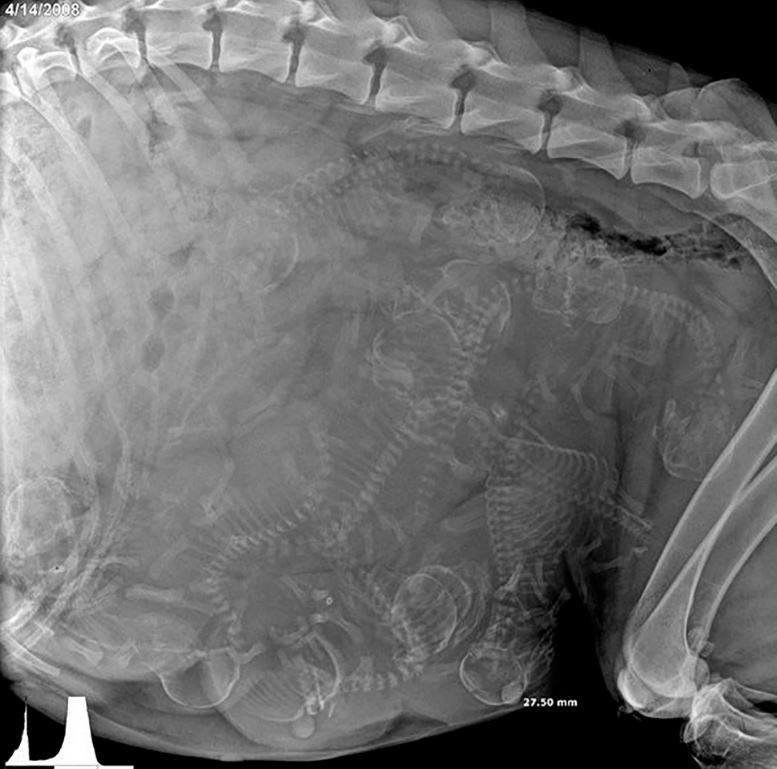

Une chienne enceinte passée aux rayons X

Source